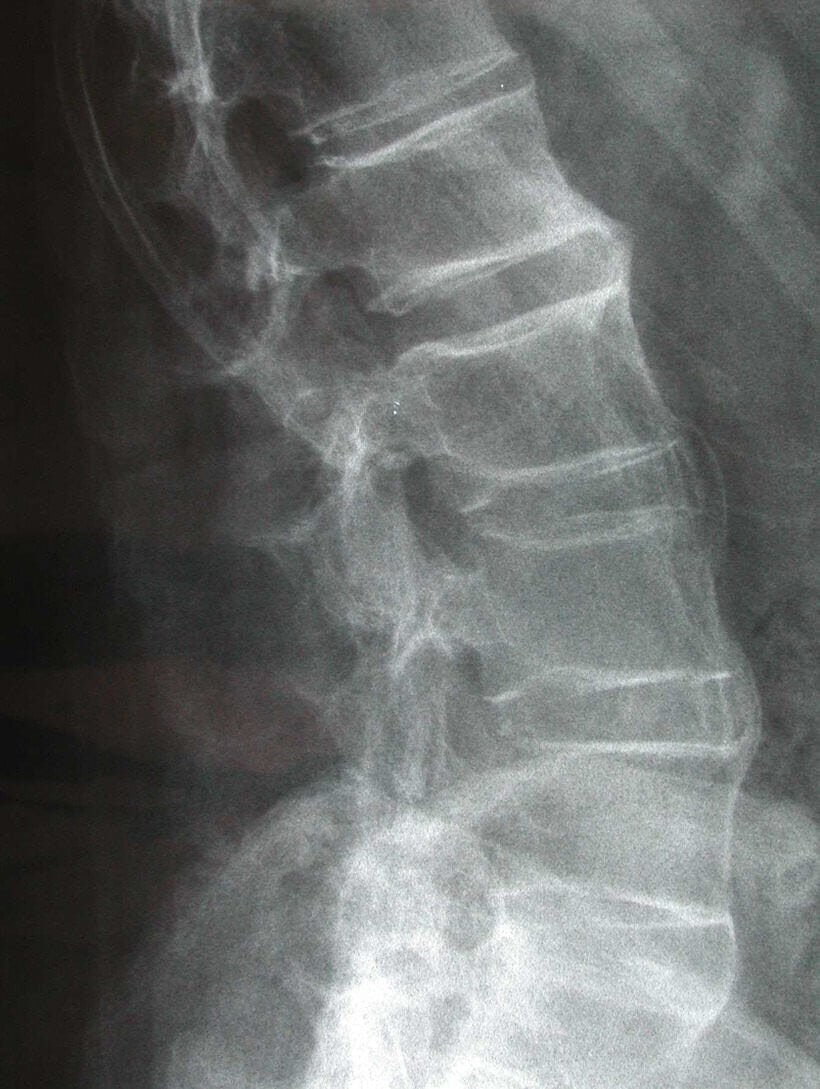

felső kép | Morbus Bechterew, wikimedia.org